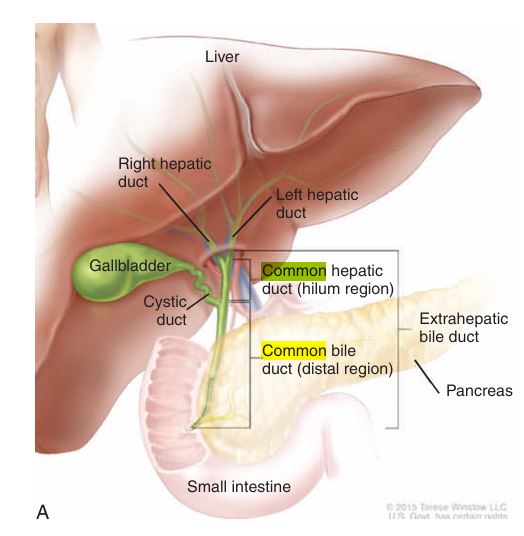

biliary diagram